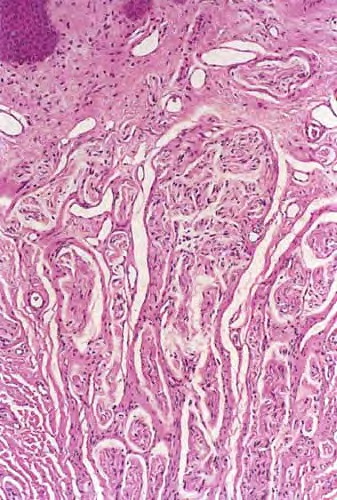

• Preaxial polydactyly, the most common type, refers to the duplication of the first digit or ray.

• Central polydactyly involves duplication of the second, third, or fourth digit or ray.

• Postaxial polydactyly involves the fifth digit or ray. The terms radial, central, and ulnar have been proposed more recently as an alternative subclassification to describe polydactyly in the upper extremity.

• Similarly, the terms tibial, central, and fibular have been proposed to describe polydactyly in the lower extremity. Initially, polydactyly in the foot was believed to be a variant of the hand. Yet, findings show the association of hand and foot polydactyly to be uncommon.